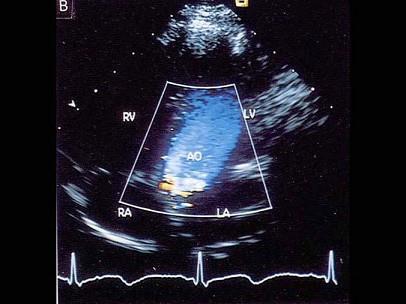

该图蓝色血流信号表示?(?)A.动脉血B.静脉血C.血流方向背离探头D.血流方向朝向探头E.以上均不是

问题 该图蓝色血流信号表示?(?)

选项 A.动脉血 B.静脉血 C.血流方向背离探头 D.血流方向朝向探头 E.以上均不是

答案 C